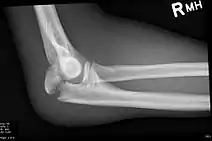

| Fracture of the olecranon | |

To assess an olecranon fracture, a careful skin exam is performed to ensure there is no open fracture. Then a complete neurological exam of the upper limb should be documented.[5][2] Frontal and lateral X-ray views of the elbow are typically done to investigate the possibility of an olecranon fracture.[1] A true lateral x-ray is essential to determine the fracture pattern, degree of displacement, comminution, and the degree of articular involvement.